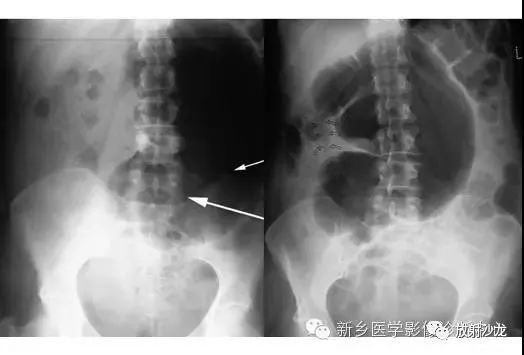

上图为一58岁男性,因1周前非特异性消化不良,行上消化道钡餐检查,做的腹部平片。患者最初表现为不确切的腹部不适和便血。现在又出现了腹痛和腹膜炎。箭头所指的典型表现是什么,诊断是什么?

箭头指向缺血穿孔性肠病患者的浅浮雕征。这也被称为双壁征或Rigler征。通常仅一侧肠壁可以看到。当双侧都能看到时,它表示腔内和腔外都有气体。当病人腹痛症状逐渐加重,肠壁穿孔是很有可能的。该患者手术过程中发现肠道脾曲缺血穿孔性肠病。